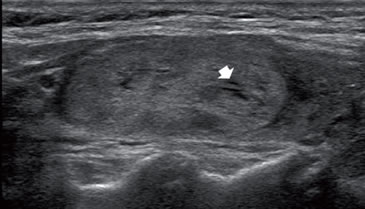

Un nódulo sólido, que en el borde muestra sombras por refracción es sospechoso de malignidad (Figura 28). Macroscópicamente, el cáncer papilar frecuentemente (56%) contiene abundante cantidad de tejido conectivo fibroso reactivo,particularmente en la periferia del tumor7. Es posible que esta reacción fibrótica sea la causante de la sombra refractiva, aunque esto no ha sido probado hasta el momento. La refracción ocurre cuando el haz de ultrasonido pasa por tejidos con diferente velocidad de propagación, lo que cambia la dirección de la onda ultrasónica. Esto causa una sombra en los bordes de la lesión que se proyecta hacia los planos profundos. Esta sombra por refracción también puede ocurrir en lesiones predominantemente quísticos, pero en el contexto de una lesión benigna no es preocupante (Figura 11).